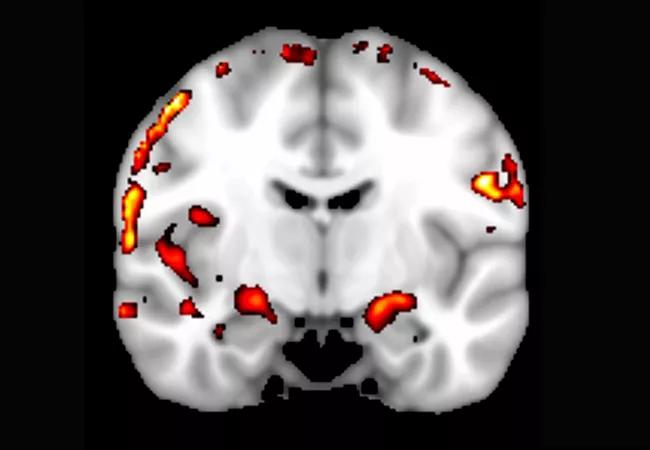

We were able to obtain bilateral activations in the hippocampus for all lures (when compared with the distraction task; P < .001) (see Figure 3, whole brain activation map for lure with the 20 percent FOV change). Figure 3 also shows that the memory activation was clearly localized to gray matter regions in the medial and superior temporal lobes, but not to the white matter, which is evidence that artifacts are minimal.

850x-Cordes-Fig-3

Figure 3. Whole brain activation during a memory-related task (t-statistic map for contrast: memory task – control task; threshold at t > 3.5, P < .001). Note that activations are mostly in the gray matter.